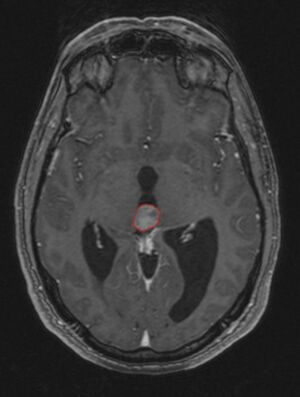

في كثير من الأحيان ، يُعرف شلل الحملقة إالعلوي جنبًا إلى جنب مع العديد من الموجودات العينية مثل رأرأة تراجع التقارب وتراجع الجفن المعروف أيضًا باسم علامة كولير وانفصال الضوء القريب (تتكيف الحدقة مع الضوء ولكنها لا تتفاعل مع الضوء) يسموا كمجموعة بمتلازمة بارينو[1] أو متلازمة الدماغ المتوسط الظهرية ، هي الأعراض الجسدية الوحيدة التي تظهر. يحدث هذا بسبب ضغط مركز الحملقة العمودي في سقف الدماغ المتوسط على مستوى الأكيمة العلوية والعصب القحفي III. يتضمن العمل عادةً التصوير العصبي كما يظهر على اليمين.[بحاجة لمصدر]